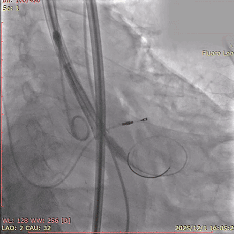

术中影像

初始造影确定无冠窦

第一次释放,瓣膜位置稍高

回收后再次释放,瓣膜位置可

多角度评估,确认瓣膜稳定

瓣膜稳定脱钩,无位移

脱钩后造影,瓣膜位置可,无瓣周漏